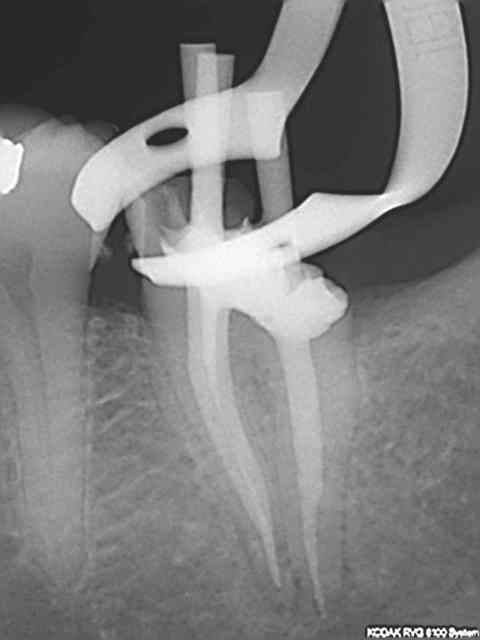

Pas de cathétérisme , r25 2/3 lt, s1 lt sur endomaster, r25 lt, saf, 30 mn point. (et pas de radio cone en place pour cause de crampon instable, qui s'est barré d'ailleurs après la radio post op).

On comprend pour le crampon, c'est limite en infra osseux en distal.

Tu vas galerer pour la reconstitution, non?

Empreinte de l'ic faite dans la séance. Vive le bistouri électrique.